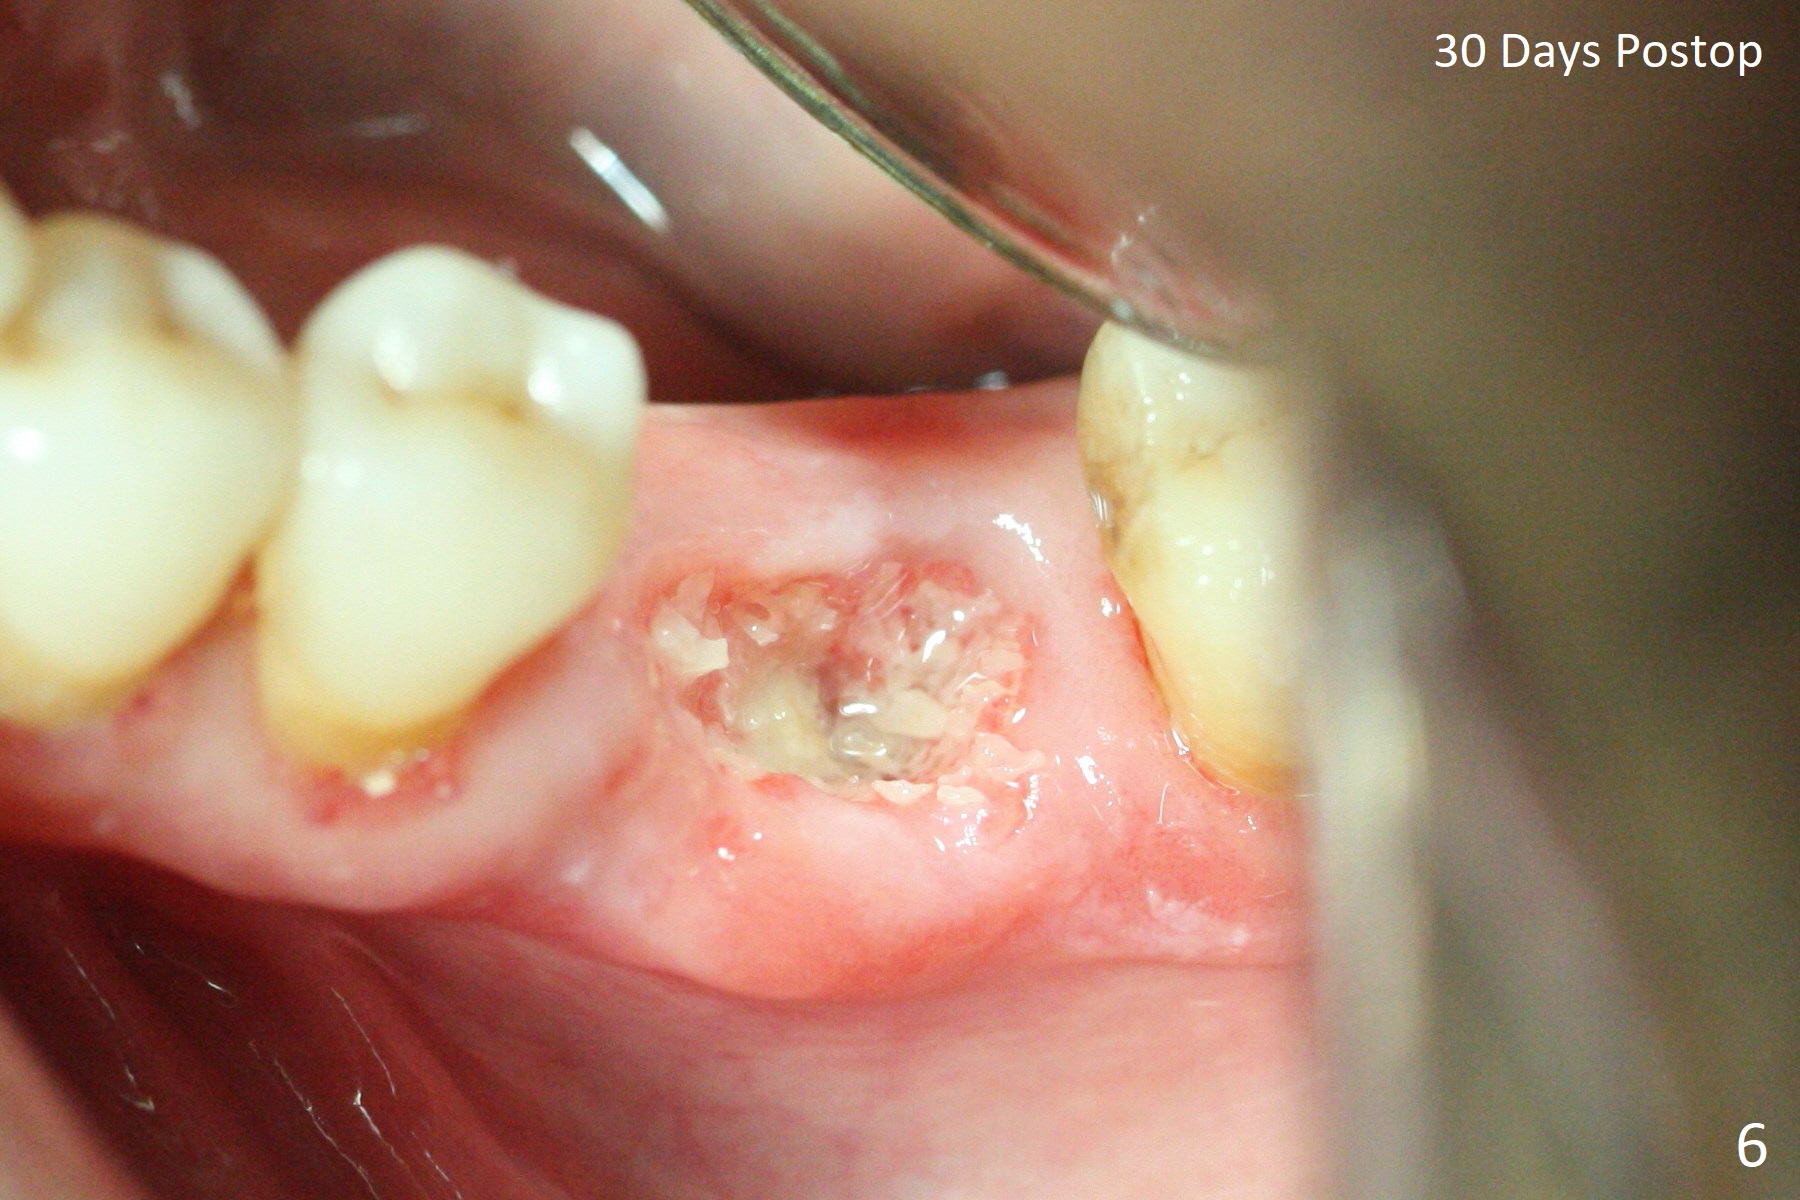

Extraction of the tooth #19 with large PARL (Fig.1,2) confirms the loss of buccal plate, but the crestal bone exists. After failure to place an implant in the middle socket with removal of the lingual septal bone, socket preservation is done with PRF and sticky bone (Fig.3). There is possibility to place a ~4 mm implant in the mesial socket (Fig.4). Or just drop a 5x11 mm Bicon Implant into the large socket, surrounded by sticky bone. When periodontal dressing is removed 18 days postop, the bone graft seems to remain to be "sticky" yellowish, while the granulation tissue has started to grow into the center of the socket from the previously buccal and lingual furcae (Fig.5 reddish). Granulation tissue seems to cover the bone graft (Fig.6), although there is smells when the periodontal dressing is removed. Bone height reduces nearly 3 months postop (Fig.7). The buccal plate collapses (Fig.8), but there seems no further bone loss 4 months postop (Fig.9). Because of buccal plate loss, an implant will be placed lingually with guide (Fig.10-12 green). Bone graft may be placed buccally after implant placement with probing.